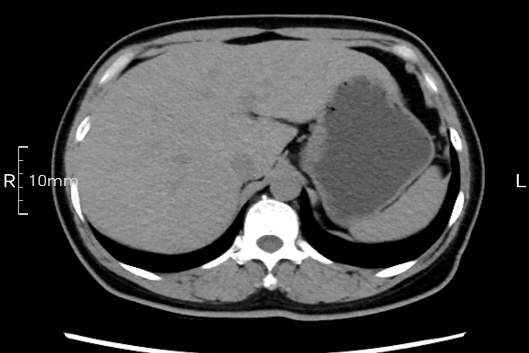

看看下面三幅便知遵醫(yī)囑的重要性。

完美禁食且喝飽飽,胃壁完美展現(xiàn)。

CT檢查前的“禁食”和“喝飽”,看似矛盾,實則合情合理,分工合作:空腹:是為了讓上腹部(肝膽胰脾腎等)的圖像清晰無干擾,并保障檢查安全。喝水:有效的充盈胃部和、腸道使圖像清晰呈現(xiàn)。兩者巧妙配合,都是為了給您一個最精準的診斷結果。